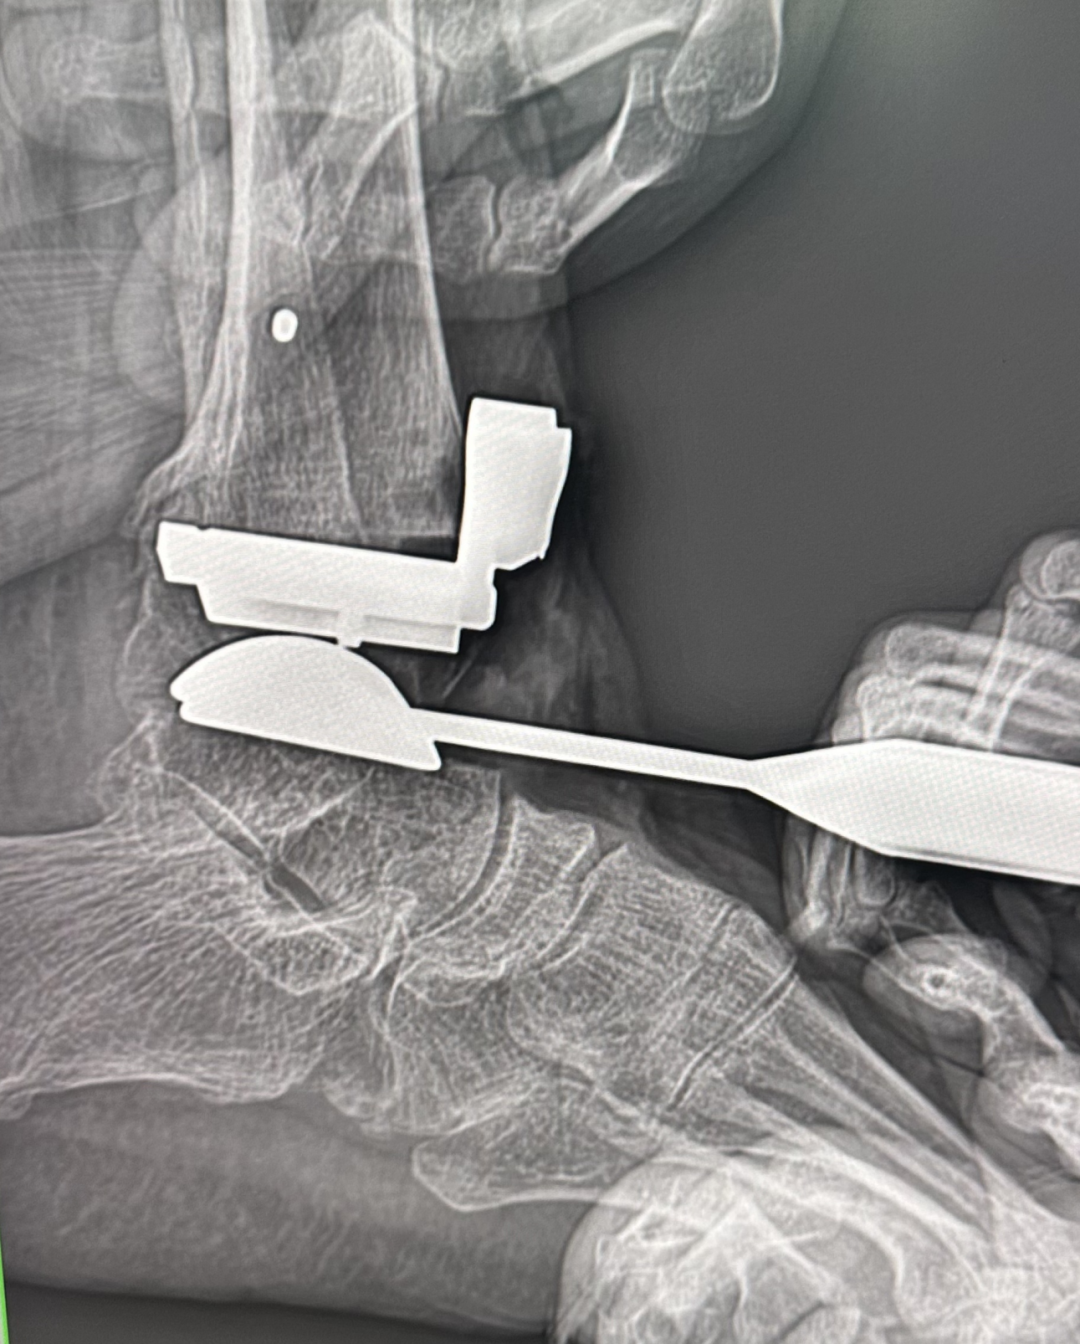

为应对复杂病情、保障手术精准安全,团队决定采用3D打印导板辅助技术。术前依托患者踝关节CT数据构建三维模型,1:1复刻关节解剖形态,量身定制专属截骨导板,精准规划植入物规格、截骨角度及厚度。

该个性化方案有效规避了传统标准化假体的贴合偏差问题,同时结合下肢生物力学分析优化假体承重设计,可精准矫正关节畸形、恢复下肢负重力线,显著降低术后假体松动、移位风险,为手术成功筑牢坚实基础。

术中,高清C臂机全程实时透视、精准导航,手术团队将定制3D打印导板与专业器械默契配合,以毫米级精度完成截骨与假体植入,既简化手术流程、缩短时长,又最大程度减少创伤与出血量。麻醉科团队量身打造个体化无痛管理方案,手术室医护人员高效协作、精细操作,各环节无缝衔接,全程守护手术平稳推进。